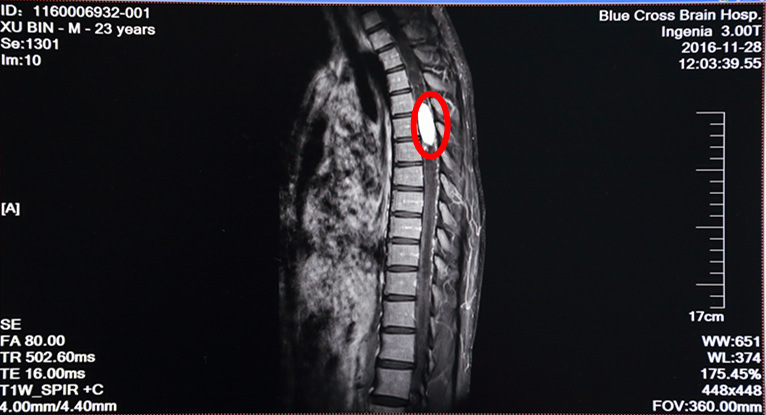

病人徐某,23歲,雙下肢失去知覺,行走不能1月半。在其他醫(yī)院檢查診斷為胸4--6段脊髓內(nèi)血管母細胞瘤,屬于最困難且風險很大的脊髓病變手術,該區(qū)域是椎管最狹窄,脊髓血供相對較豐富的部位。另外,病人第四腦室及右側(cè)海馬區(qū)顳角位置也發(fā)現(xiàn)有腫瘤,四腦室明顯擴大、腫瘤明顯壓迫腦干。病家曾找我國最知名的一位脊髓外科專家看過,認為風險巨大,遂到我院尋求治療,做增強MRI及DSA見腫瘤血供極其豐富,椎管內(nèi)幾乎僅見腫瘤而看不見正常的脊髓組織結(jié)構(gòu)。

術前MRI增強掃描:紅圈內(nèi)白色物體為腫瘤,腫瘤兩極廣泛性脊髓空洞